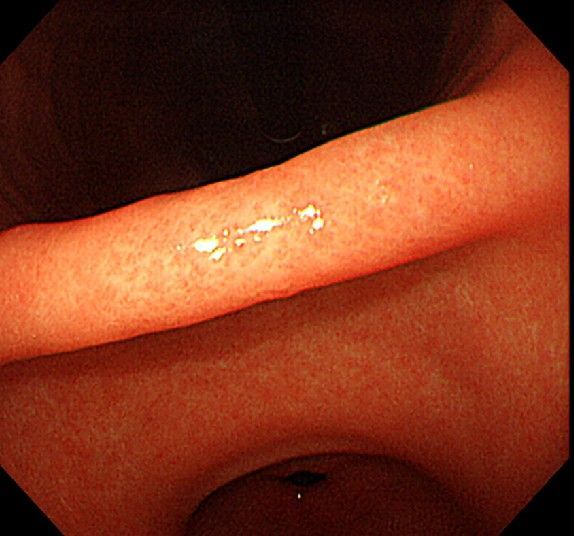

위 내시경을 찍었는데 위염 종류 사진을 알 수 있을까요? (사진 많습니다..)

한달 전 쯤에 소화불량과 속쓰림이 3개월 동안 약을 먹어도 낫지 않아 위 내시경을 찍었는데 위에 염증이 많이 있다는 이야기를 들었습니다...그런데 상태가 얼마나 안 좋은지 어떤 종류의 위염인지에 대해서는 물어봐도 안 알려주셔서 여기에라도 올려서 여쭈어봅니다... 제 상태가 얼마나 심각한 걸까요..

사진상으로 보아서는 정상에 가까운 점막상태이거나 약간의 표재성 위염이 있는 정도로 보입니다.

홍반성 위염이 있으며 경증의 역류성 식도염이 있습니다